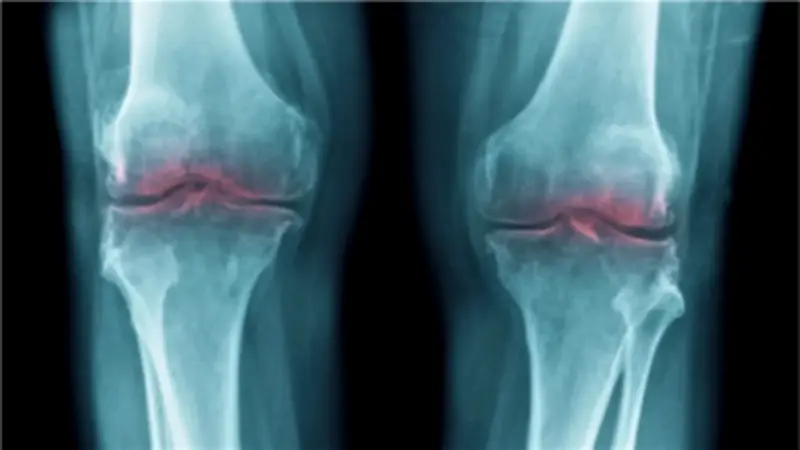

كشفت دراسة علمية حديثة عن اكتشاف ثوري يمكنه تجديد الغضروف التالف وعلاج آلام المفاصل، مما يمنح أملاً جديداً لملايين المصابين بالتهاب المفاصل حول العالم. وأظهرت الأبحاث أن فقدان الغضروف المرتبط بالتقدم في العمر يعود إلى بروتين واحد، مما يفتح الباب أمام علاجات مستقبلية قد تعيد الحركة وتخفف المعاناة لدى كبار السن.

أجريت الدراسة على فئران مختبرية، حيث وجد الباحثون أن بروتيناً يُدعى 15-PGDH يزداد بشكل ملحوظ مع تقدم العمر، ويتداخل مع الجزيئات المسؤولة عن إصلاح الأنسجة وتقليل الالتهاب. هذا الأمر دفع فريق البحث من جامعة ستانفورد الأمريكية إلى التحقق من دور هذا البروتين في تطور التهاب المفاصل، وفقاً لما نشرته مجلة ScienceAlert العلمية.

خلال التجارب، تم إدخال مثبط لإنزيم بروتين 15-PGDH إلى فئران مسنة، مما أدى إلى زيادة سمك غضروف الركبة الذي كان قد تآكل سابقاً. وفي تجارب مماثلة على فئران صغيرة مصابة، وفر المثبط حماية فعالة ضد الأعراض النمطية لالتهاب المفاصل الناتج عن الإصابات.

عندما قام الباحثون بإحداث إصابة تعادل تمزق الرباط الصليبي الأمامي في الفئران ثم طبقوا العلاج، لم يتطور التهاب المفاصل كما هو متوقع. وعلى عكس المحاولات السابقة التي اعتمدت على الخلايا الجذعية لتجديد الغضروف، فإن تثبيط بروتين 15-PGDH لم يعد بحاجة لهذه الخلايا، بل تم تحويل الخلايا الغضروفية المنتجة للغضروف إلى حالة أكثر صحة وكفاءة.